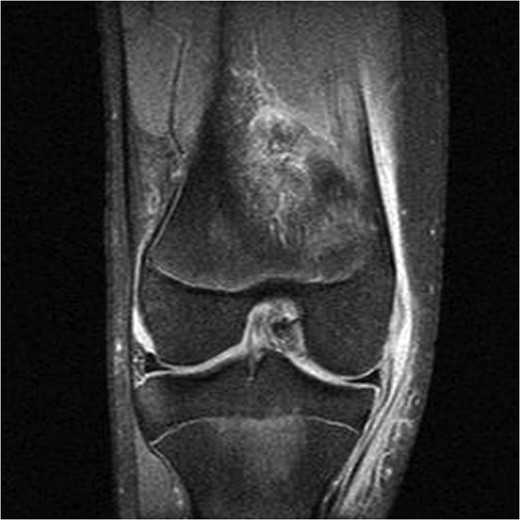

A 16-year-old elite level footballer presented to our clinic with persistent symptoms of instability following a knee injury. The patient had sustained a valgus force to his knee during a tackle. He had been treated by his football club's doctor after an magnetic resonance imaging (MRI) scan had demonstrated a MCL injury (Fig. 1).

The patient's initial management was non-operative with a period of knee protection with a range of movement brace and intensive rehabilitation. Approximately 3 months after the index injury he returned to competitive football but shortly after his return sustained a further valgus injury and despite further conservative treatment was unable to return to sport. He was referred to our service with ongoing instability symptoms. Upon clinical assessment we noted an asymmetric valgus alignment of the knee and abnormal laxity of the MCL. Radiographic investigations revealed an abnormality of the lateral distal femur and alignment radiographs confirmed the valgus mal-alignment with abnormal opening of the medial tibio-femoral joint space on single-leg stance radiographs (Figs 2–4). We obtained the patient's MRI scan and reviewing this with Radiology colleagues revealed subtle changes of increased lateral femoral physis fluid density on T-2 weighted images consistent with a Salter Harris Type V injury (Fig. 5).

MRI showing increased fluid density around the lateral distal femoral physis (red arrow).